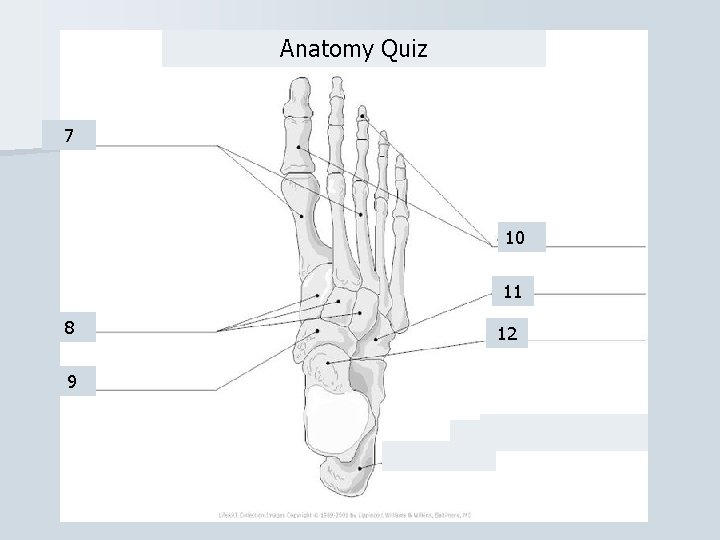

Bones of the Ankle and Foot

Anatomy Quiz 7 10 11 8 9 12